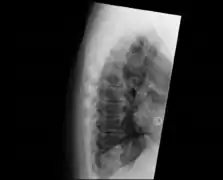

DISH in an 80 year old female, also with T11 fracture.

DISH can be a complicating factor when suffering from trauma involving the spine. It increases the risk of unstable fractures involving the intervertebral disc and the calcified/ossified ligaments which influences the need for surgical treatment.[8]